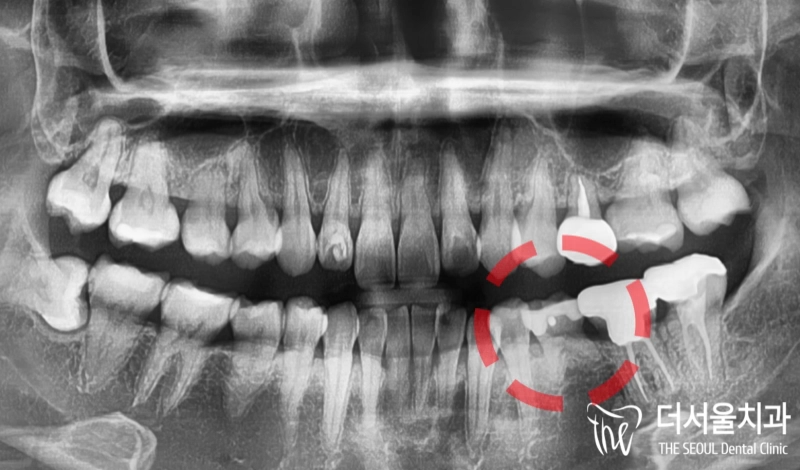

반갑습니다. 잠실 더서울 치과 박현성 원장입니다. 예전에 내원을 하셨던 환자 중에 따님분께 추천을 받아 오게 되었으며, 임플란트 수술을 받았던